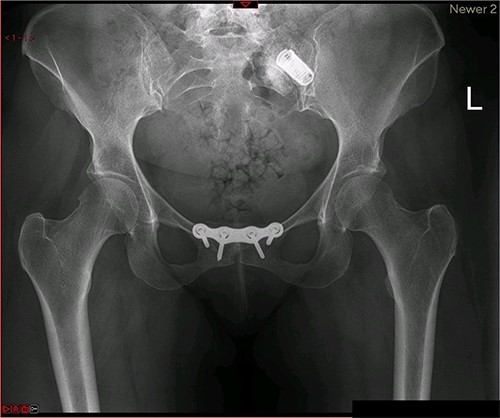

A magnetic resonance imaging (MRI) scan performed in October 2013 (Fig. 1) identified non-compressive, degenerated discs at L4/5 and L5/S1 vertebral levels. However, clinically as the patient was more tender over the left SI joint and the pubic symphysis (Fig. 2), a left sacroiliac joint fusion and symphysis pubis plating procedure was performed in August 2014 (Fig. 3). Following a short period of relief, the pain returned. Subsequently, the patient underwent a 360° fusion (front and back) of the L4/L5 and L5/S1 discs in August 2015 (Fig. 4), a year following the previous surgery. Once again, following a brief period of relief, the symptoms returned. The assumption then was that the initial fusion of the left sacroiliac joint had failed. Therefore, a revision fusion of the left sacroiliac joint and a primary fusion of the right sacroiliac joint was undertaken in August 2017 (Fig. 5).

Postoperative X-ray of the pelvis following the first fusion surgery: postoperative X-ray of the pelvis, performed in November 2014 following the first fusion surgery, showing plating of the symphysis pubis and distraction arthrodesis of the left sacroiliac joint with DIANA implant.